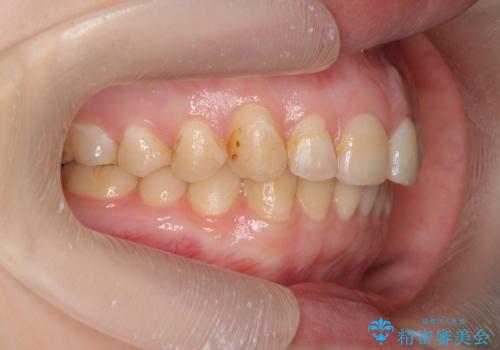

マウスピース矯正で行う出っ歯の治療

- 飛び出したように見える前歯の改善を求めて来院されました。

元々、セラミッククラウンですぐに歯並びを改善したいと希望されていましたが、目立たないマウスピース矯正治療のご提案を行なったところ矯正治療による歯並びの改善を選択されました。

矯正治療を行ったことで出っ歯の改善とともに安定した噛み合わせも手に入れることができました。